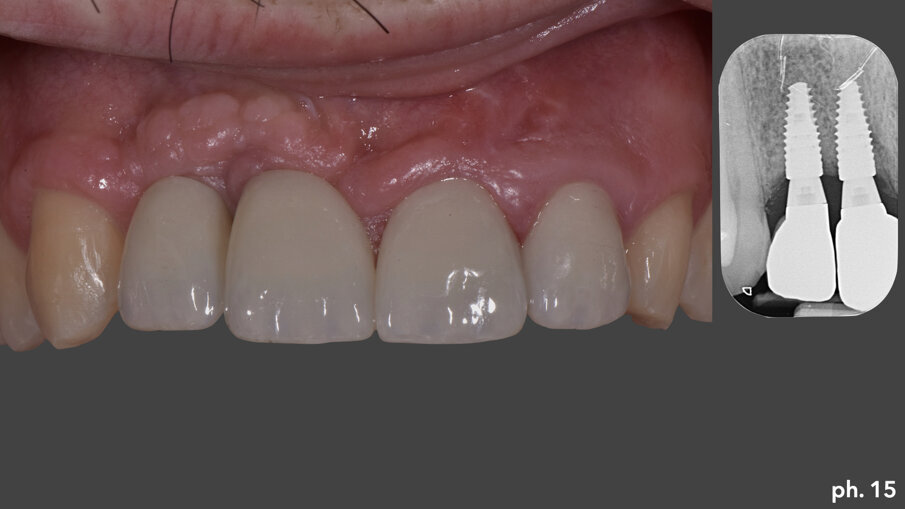

Dopo aver rimosso le viti di fissazione, la griglia stessa viene tagliata e separata in due porzionilungo la linea predefinita in senso longitudinale. Le stesse vengono poi rimosse delicatamente avvalendosi dell’aiuto di uno scollaperiostio e di un bisturi (Fig. 11). A questo punto una volta denudato il piano osso e valutata la sua qualità e quantità, possiamo passare all’inserimento degli impianti che in questo caso è stato effettuato in tecnica classica, senza l’ausilio di una mascherina per un inserimento computer guidato. Gli impianti scelti nella risoluzione di questa situazione sono due impianti Straumann BLT 4,1 x 10 mm (Fig. 12). Una volta inseriti gli impianti si è provveduto ad effettuare un assottigliamento del lembo palatino5; per permettere al paziente una miglior detersione dei presidi implanto-protesici, oltre che per consentirci l’utilizzo della porzione epitelio connettivale rimossa per ispessire coronalmente il tessuto gengivale nella zona di inserimento degli impianti. Eliminata chirurgicamente la porzione epiteliale del prelievo, abbiamo stabilizzato quella connettivale a livello osseo crestale utilizzando una sutura riassorbibile che ancorasse il tessuto al periostio (Fig. 13). L’aumento in senso verticale del tessuto cheratinizzato è evidenziato dall’immagine numero 14 dove possiamo valutare il livello coronale del tessuto molle prima della rigenerazione, la linea bianca, al momento della rimozione della griglia, la linea arancione, e infine alla maturazione dell’innesto di tessuto connettivo, la linea di colore verde (Fig. 14). Una volta maturati i tessuti molli sono stati quindi inseriti quattro elementi provvisori singoli, dall’elemento 1.2 all’elemento 2.2, di cui due su impianti e due su denti; le modifiche nel tempo di questi provvisori secondo la tecnica della compressione dinamica, ci hanno permesso di condizionare la guarigione degli stessi tessuti molli6 prima di passare alla fase di protesizzazione definitiva. I manufatti protesici definitivi sono quattro corone singole in zirconio-ceramica su impianti e su elementi naturali: in particolare le corone su 1.1 e 1.2 sono avvitate agli impianti (Fig. 15).